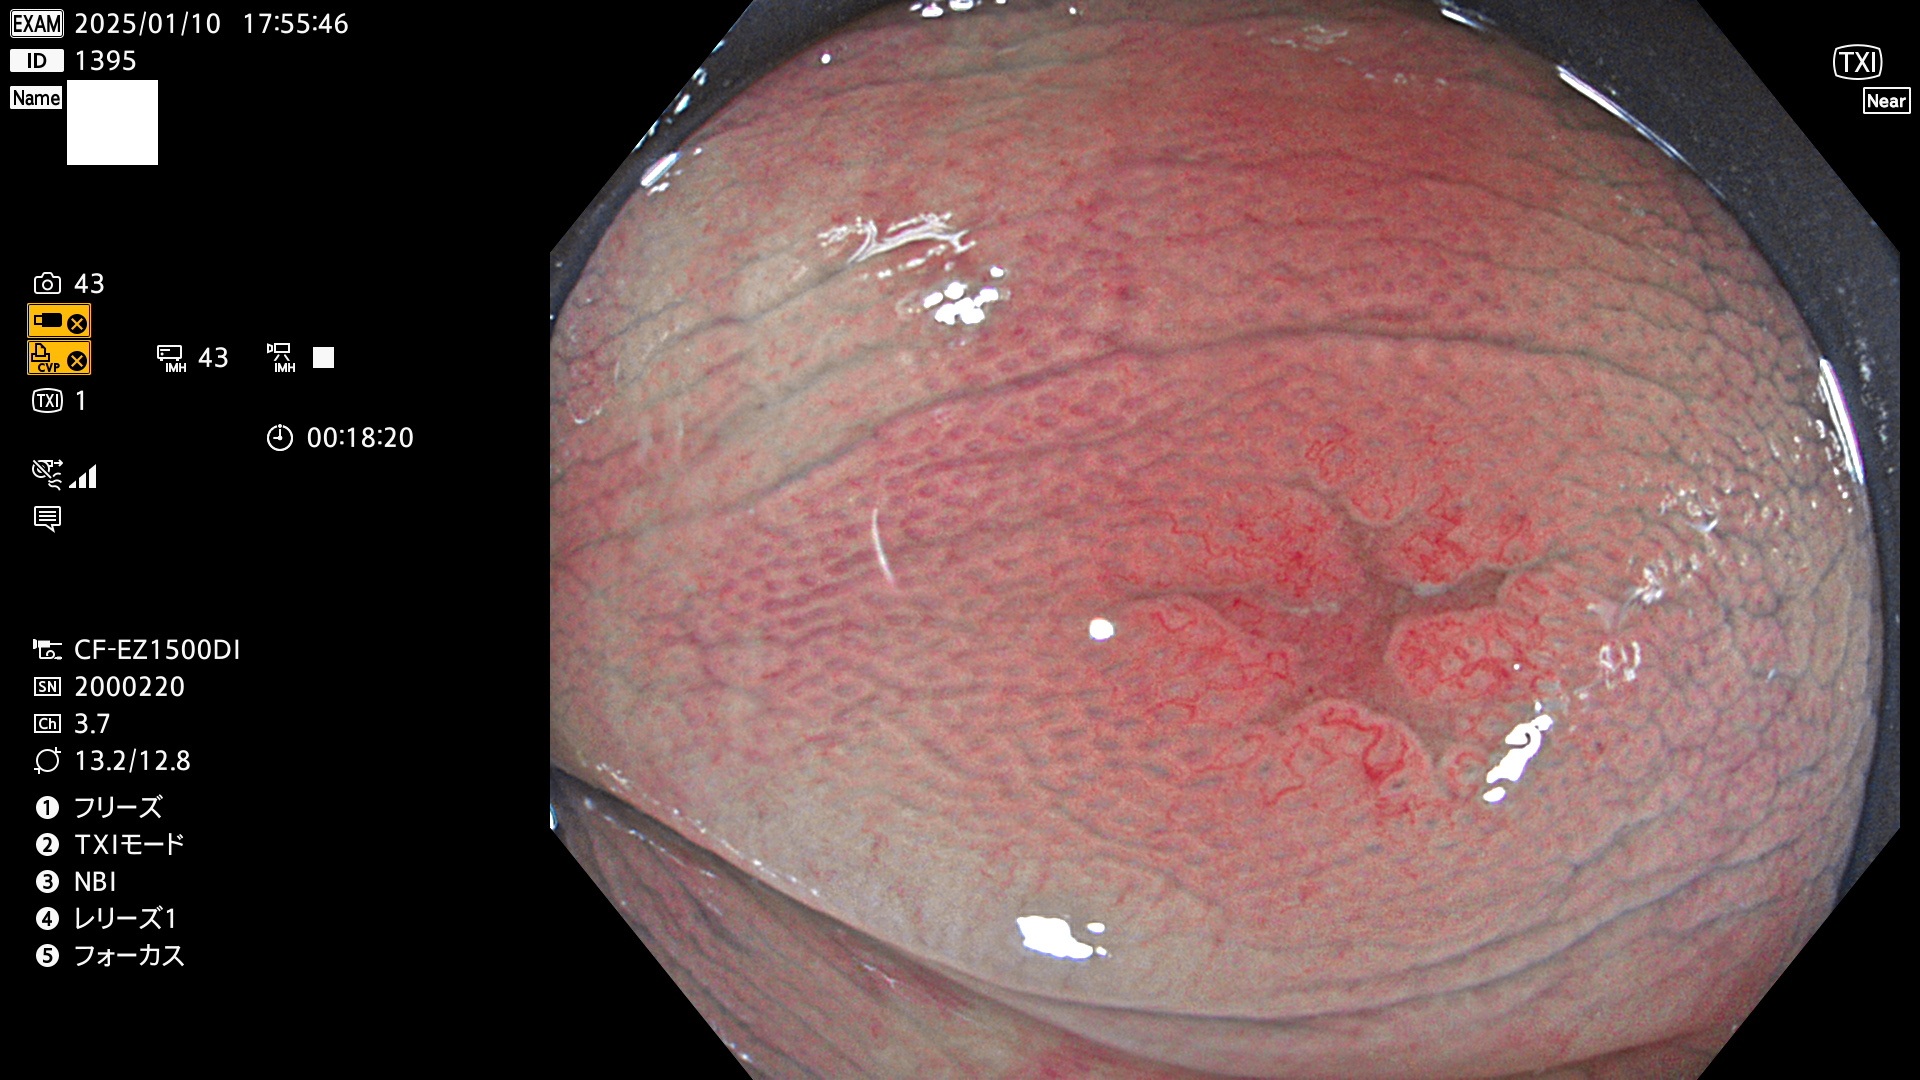

完全に平坦な物をUb、陥凹している物をUcと呼びます。最も発見が難しく危険な病変です。

毎週の検査(木・金・土・日)に発見されたUb、Uc型・腺腫を、その週の日曜の夜にUPし1週間、提示します。

抽出の対象期間 2025年1月9日〜1月12日の4日間(45件の検査)5件 (5/45=11%)